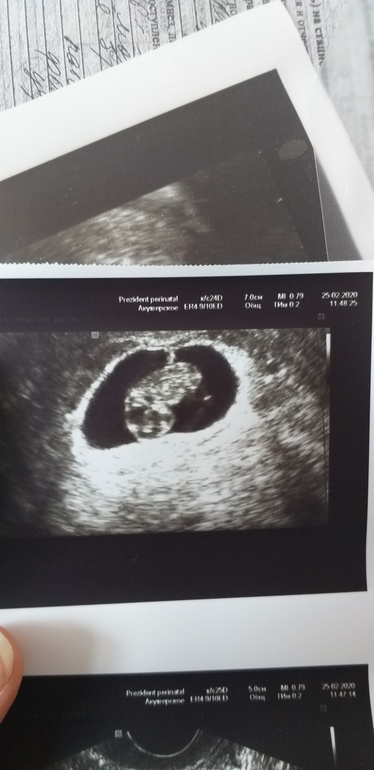

Позитивный пост 🤭 Сходила на УЗИ

Ктр 17.7, чсс 177 уд/мин. Локализация по задней стенке. Д жм =20мм (в пя). Срок по узи 8.2 (по мес. 7.5)